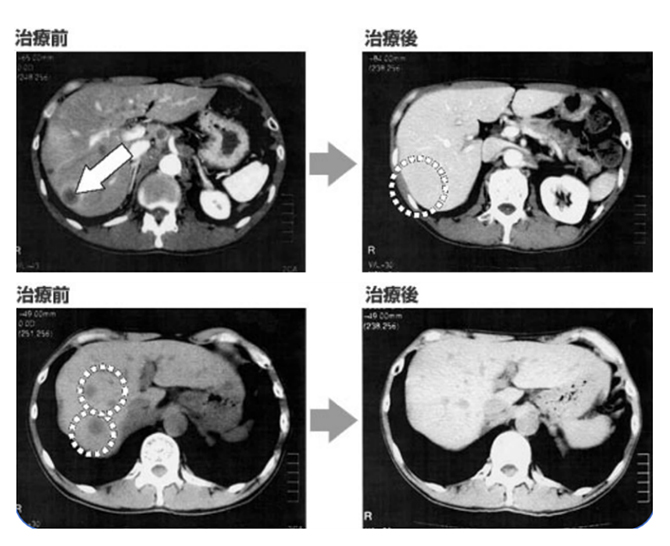

有效抑制肿瘤生长,阻断癌细胞扩散

有效治疗癌症,促进病情好转与恢复